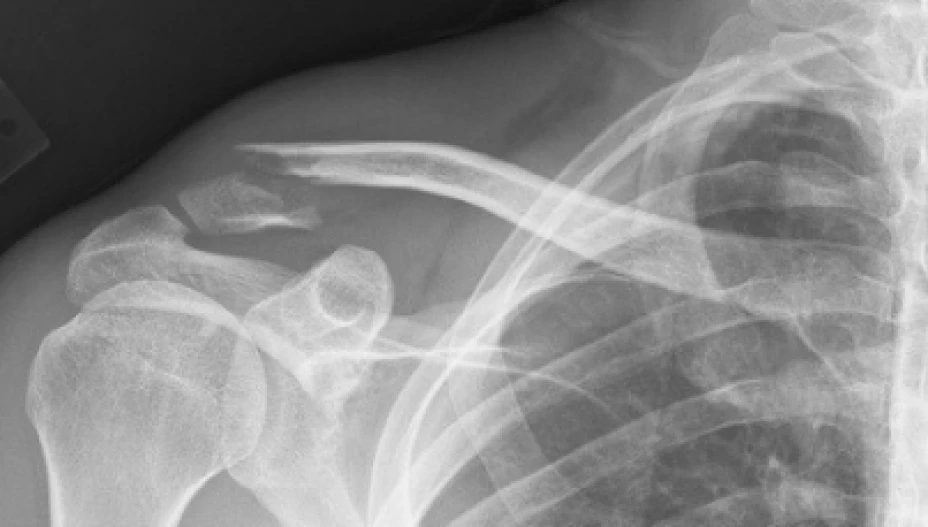

La también integrante de la Asociación Mexicana de Metabolismo Óseo y Mineral explicó que una de las fracturas más comunes y costosas que se dan en el padecimiento de la osteoporosis es la de cadera, la cual registró 29 mil casos en 2005, y se prevé que el número aumente a más de 155 mil para 2050.

En tanto que atender otras fracturas frecuentes en la osteoporosis, detalló la especialista, le cuesta al Instituto mil 669 dólares la de muñeca, mil 34 en vértebra, mil 617 para el húmero, y mil 617 para atender las del tobillo.